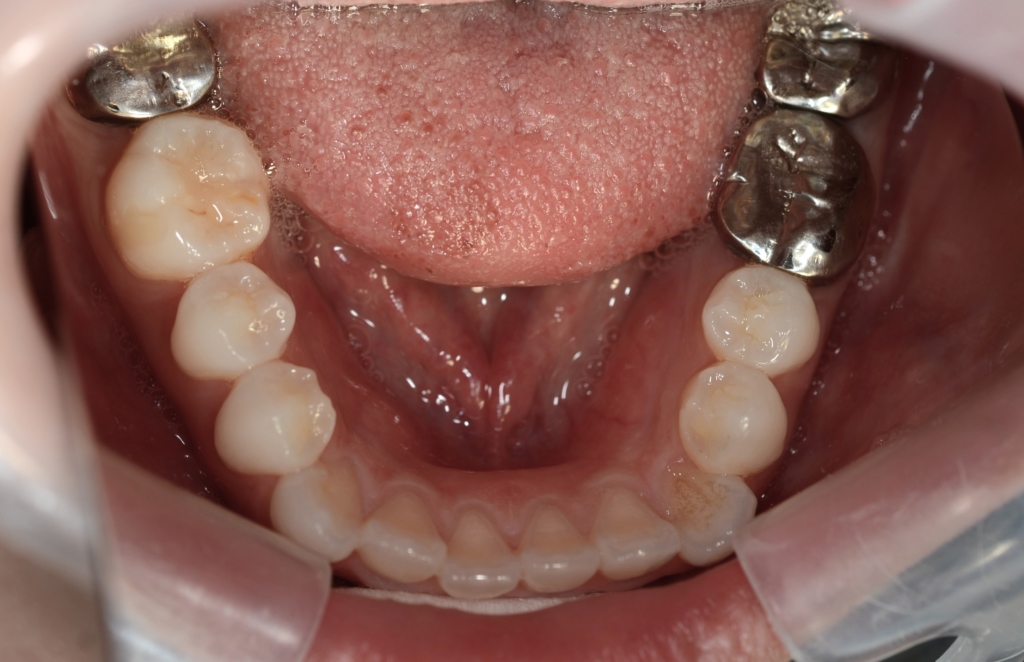

2.上下の左右の奥歯を1本ずつ(計4本)抜歯をしてスペースを作り、

上下の前歯を最大限に後方へ引っ込める

前歯部の噛み合わせに目途が付いた時点で、下の歯にも装置を付けて、合わせて治療を進めます。

噛み合わせがしっかりしたところで、上下とも第一小臼歯を抜歯して前歯を後方へ最大限に引っ込めて行きます。

上下の左右の奥歯を1本ずつの計4本(全て第一小臼歯)を抜歯